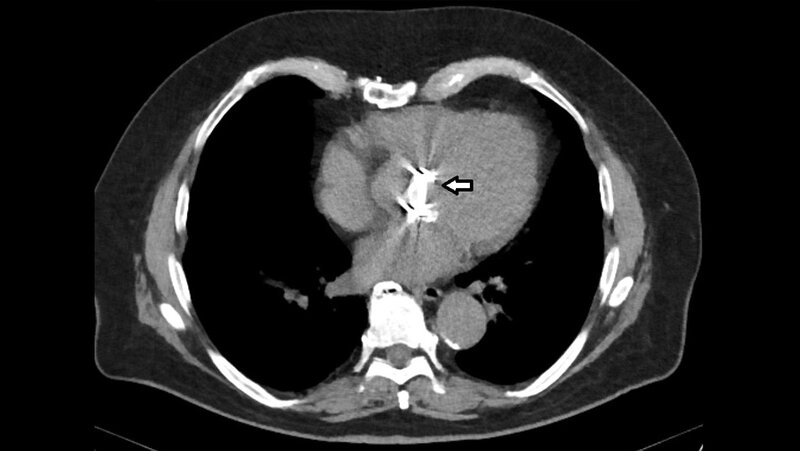

Artefakte können die diagnostische Qualität der Aufnahmen beeinflussen. Auch in der Radiotherapie müssen für eine exakte Therapieplanung die Artefakte reduziert werden. Metallische Implantate können in der Magnetresonanz-Bildgebung erhebliche Artefakte verursachen, insbesondere Signalverluste, Signalverstärkungen, geometrische Verzerrungen und Veränderungen in der Fettsuppression. Die Zusammensetzung des Prothesenmaterials bestimmt das Ausmaß der Artefakte und die Qualität der MR-Aufnahmen. Die Computertomografie hat ebenfalls mit Metallartefakten zu kämpfen. Auch bei der Sonografie sind störende Bildeinflüsse möglich.

Artifacts can affect the diagnostic quality of the images. Artifacts must also be reduced in radiotherapy for precise treatment planning. Metallic implants can cause considerable artifacts in magnetic resonance imaging, in particular signal loss, signal pile-up, geometric distortions and fat suppression failure. The composition of the prosthesis material determines the extent of the artifacts and the quality of the MR images. CT also has to contend with metal artifacts. Image quality issues are also possible with ultrasound.